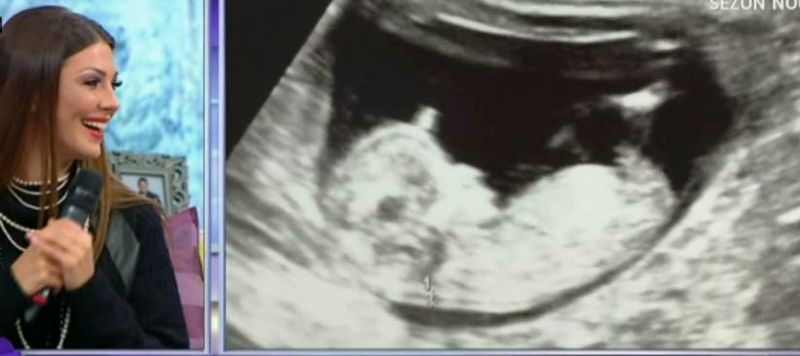

Momentan nu stie ce o sa fie, insa vedeta KanalD isi doreste ca micutul pe care-l poarta in pantace sa fie baiat. Ilinca Vandici a facut publica prima ecografie cu bebelul.

„Eu imi doresc sa fie baiat, dar nu stiu. Sunt insarcinata in 12 saptamani. Sunt foarte fericita, incantata si emotionata.

Este cea mai fericita perioada din viata mea. Anul 2016 a fost unul foarte bun pentru mine. A venit proiectul ‘Bravo, ai stil’, l-am cunoscut pe iubitul meu si am si ramas insarcinata”, a declarat Ilinca Vandici, in prima editie TeoShow din acest an.